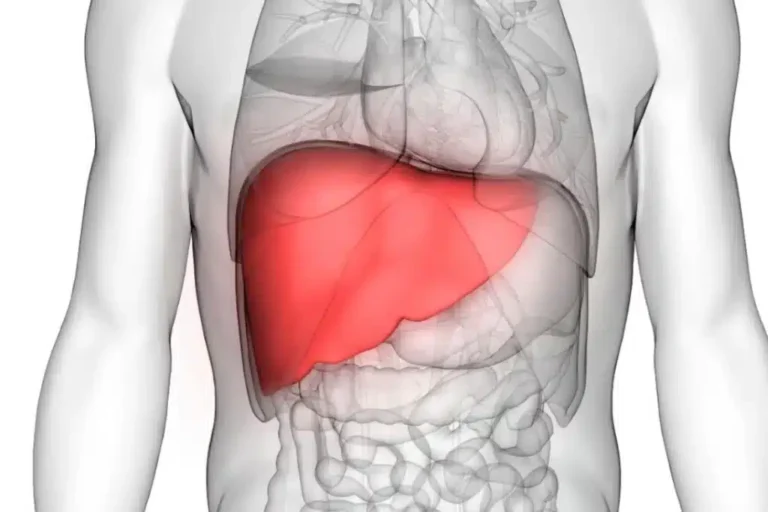

Upaya mengenal peradangan hati akan membantu kita untuk menjaga kualitas orgaan dalam. Organ liver memegang peranan sangat besar dalam menyaring racun yang masuk ke tubuh. Jika jaringan ini mengalami iritasi, sistem metabolisme tubuh akan terganggu secara perlahan.

Mengenal Peradangan Hati dan Penyebabnya

Dampak Pola Makan Terhadap Upaya Mengenal Peradangan Hati

Gejala Fisik Gangguan Fungsi Hati